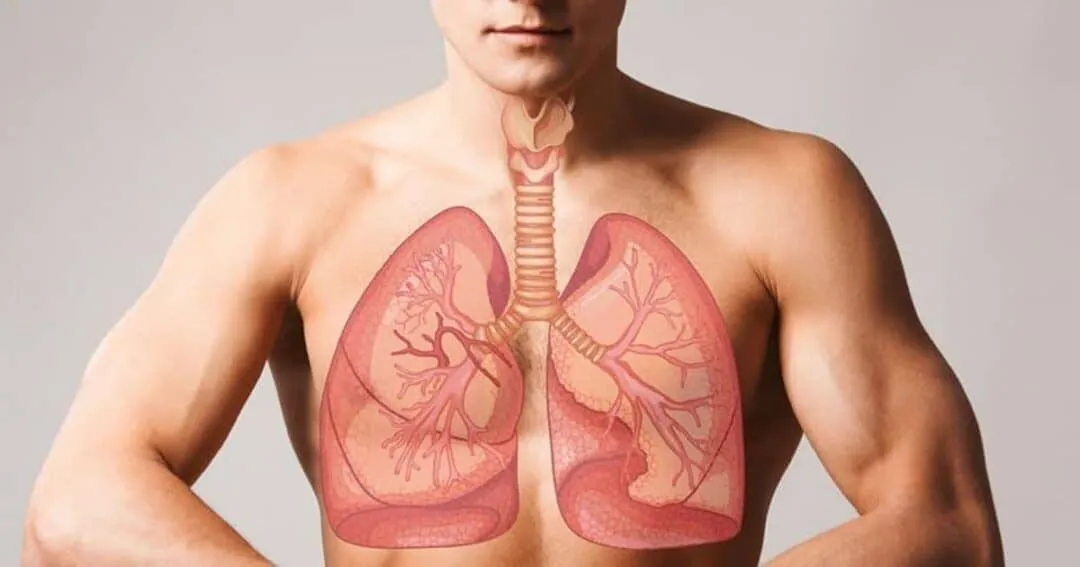

Lung Cancer is one of the most serious and life-threatening diseases worldwide, affecting millions of people every year. It develops when abnormal cells grow uncontrollably in the lungs, interfering with normal breathing and oxygen exchange. Despite major advances in medical science, Lung Cancer remains the leading cause of cancer-related deaths globally due to late diagnosis and aggressive progression.

Lung Cancer begins when cells in the lungs undergo genetic mutations that cause them to grow uncontrollably. These abnormal cells can form tumors and spread to nearby tissues or distant organs through the bloodstream or lymphatic system. The lungs are particularly vulnerable because they are constantly exposed to airborne toxins.

Over time, repeated exposure to harmful substances damages the DNA inside lung cells. When the body fails to repair this damage, cancerous changes may occur. Lung Cancer often develops silently, showing no symptoms until it reaches an advanced stage, which makes early detection difficult.

Diagnosing Lung Cancer involves a combination of imaging tests, laboratory analysis, and tissue sampling. Doctors often begin with chest X-rays or CT scans to detect abnormal growths in the lungs.

If a suspicious mass is found, a biopsy is performed to confirm the presence of cancer cells. Advanced molecular testing can also identify genetic mutations that guide targeted therapy decisions.